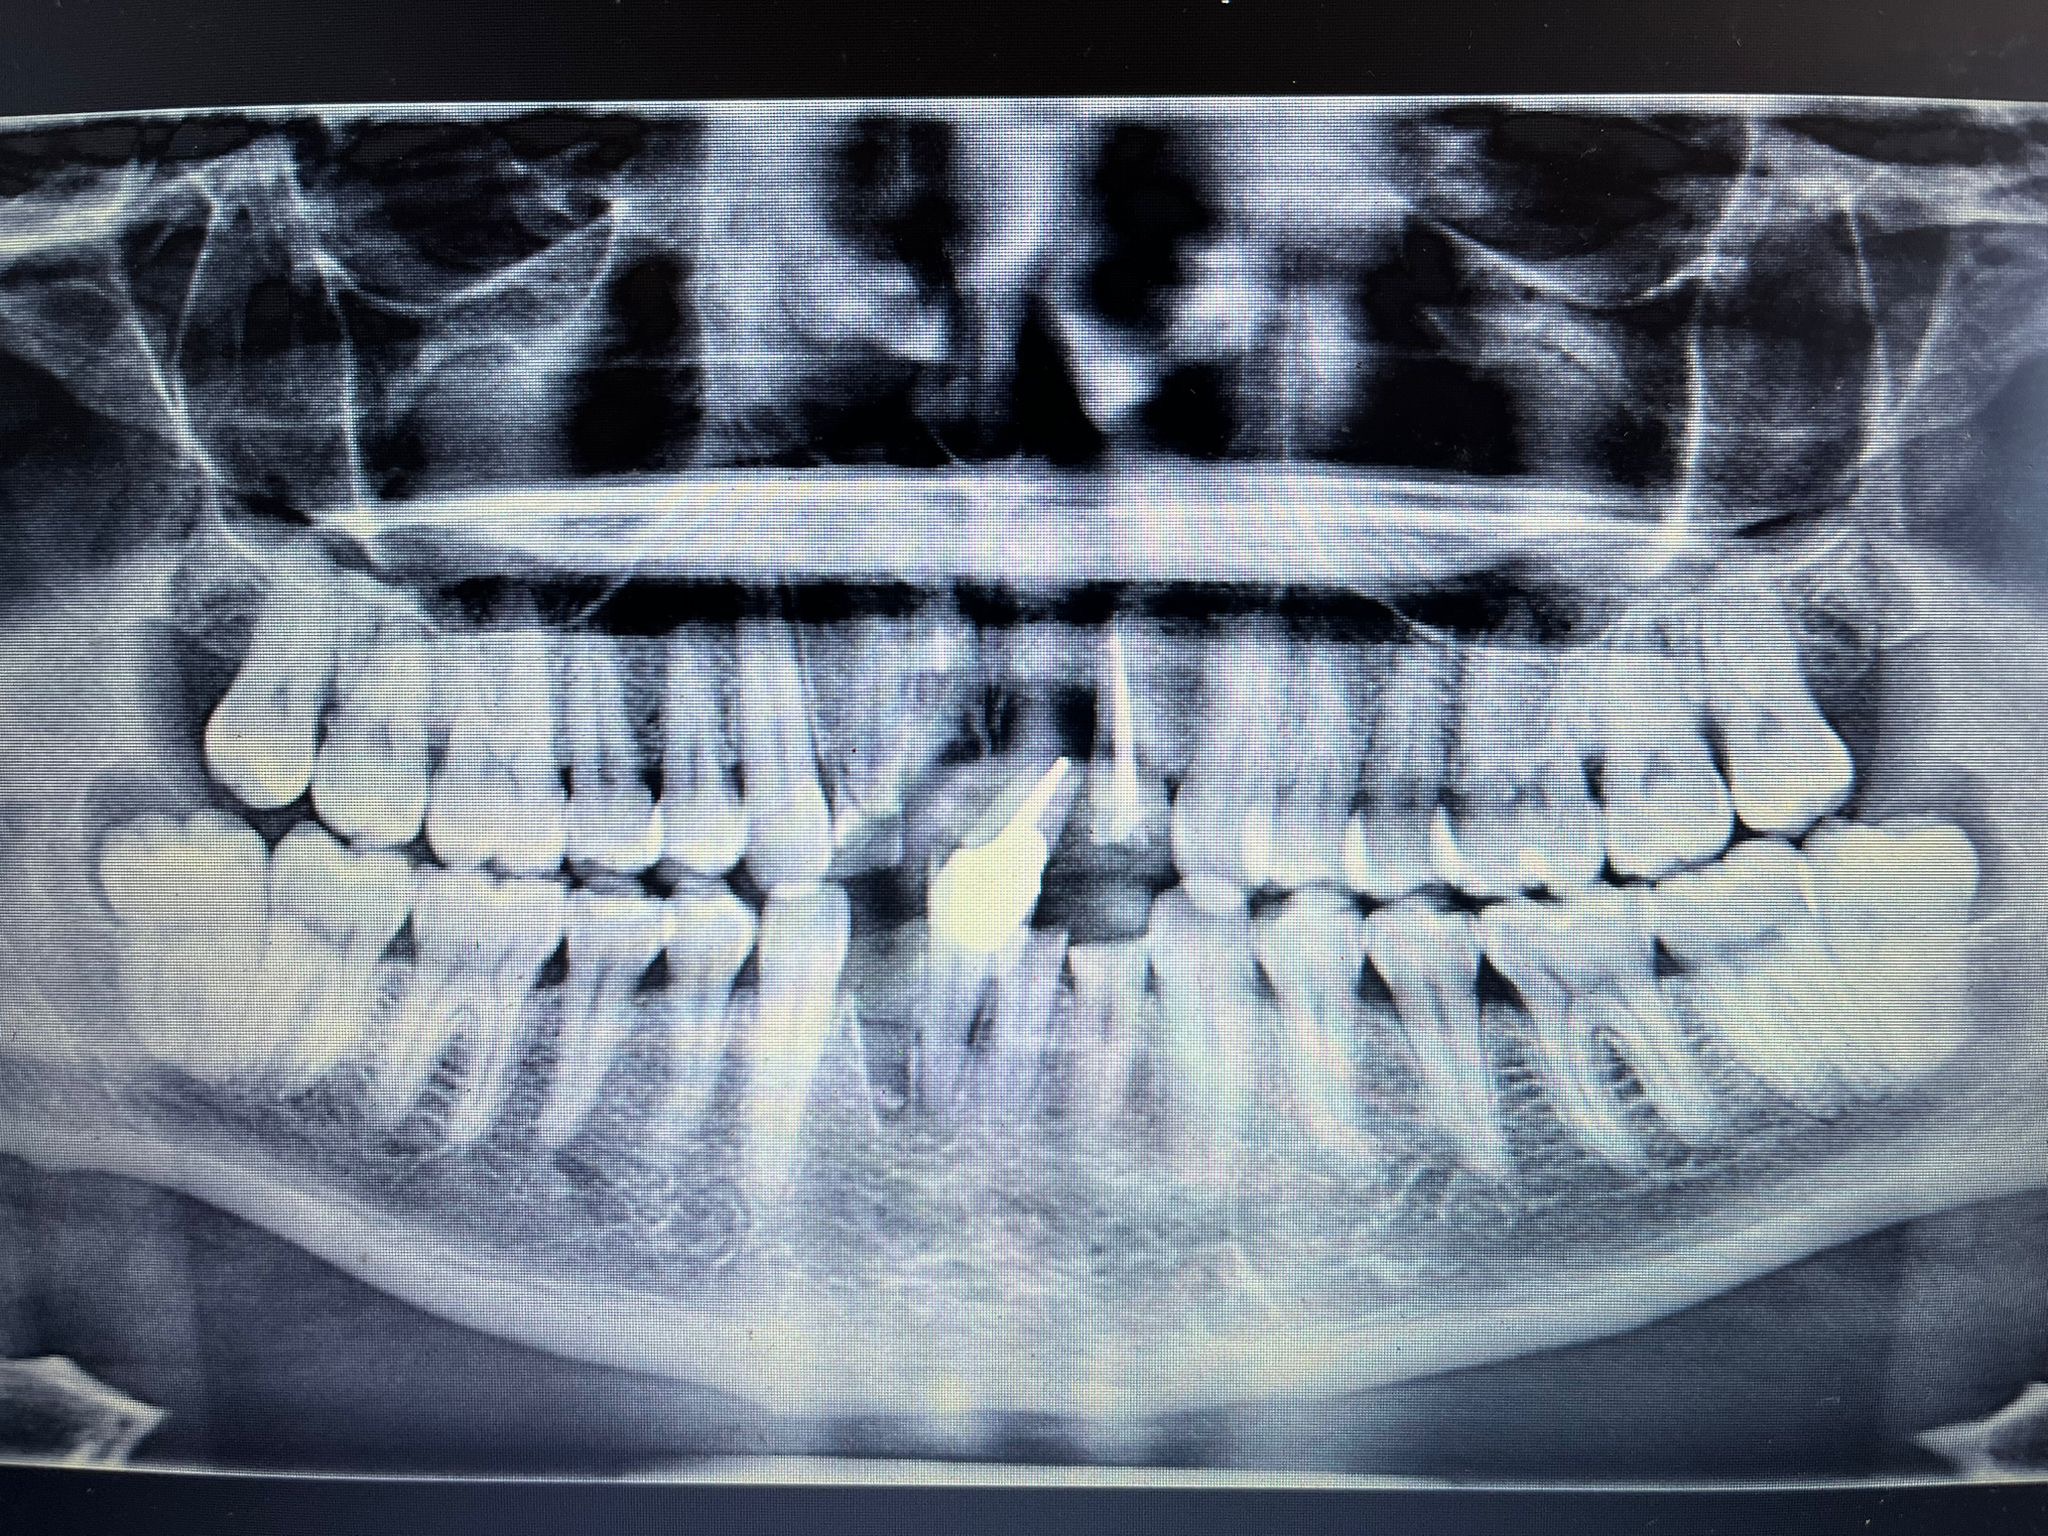

The accident left him with a fractured sternum and the loss of eight front teeth, possibly more. He’s now facing months, possibly years, of dental work. It’s a lot to take in, and it’s going to be a long road.